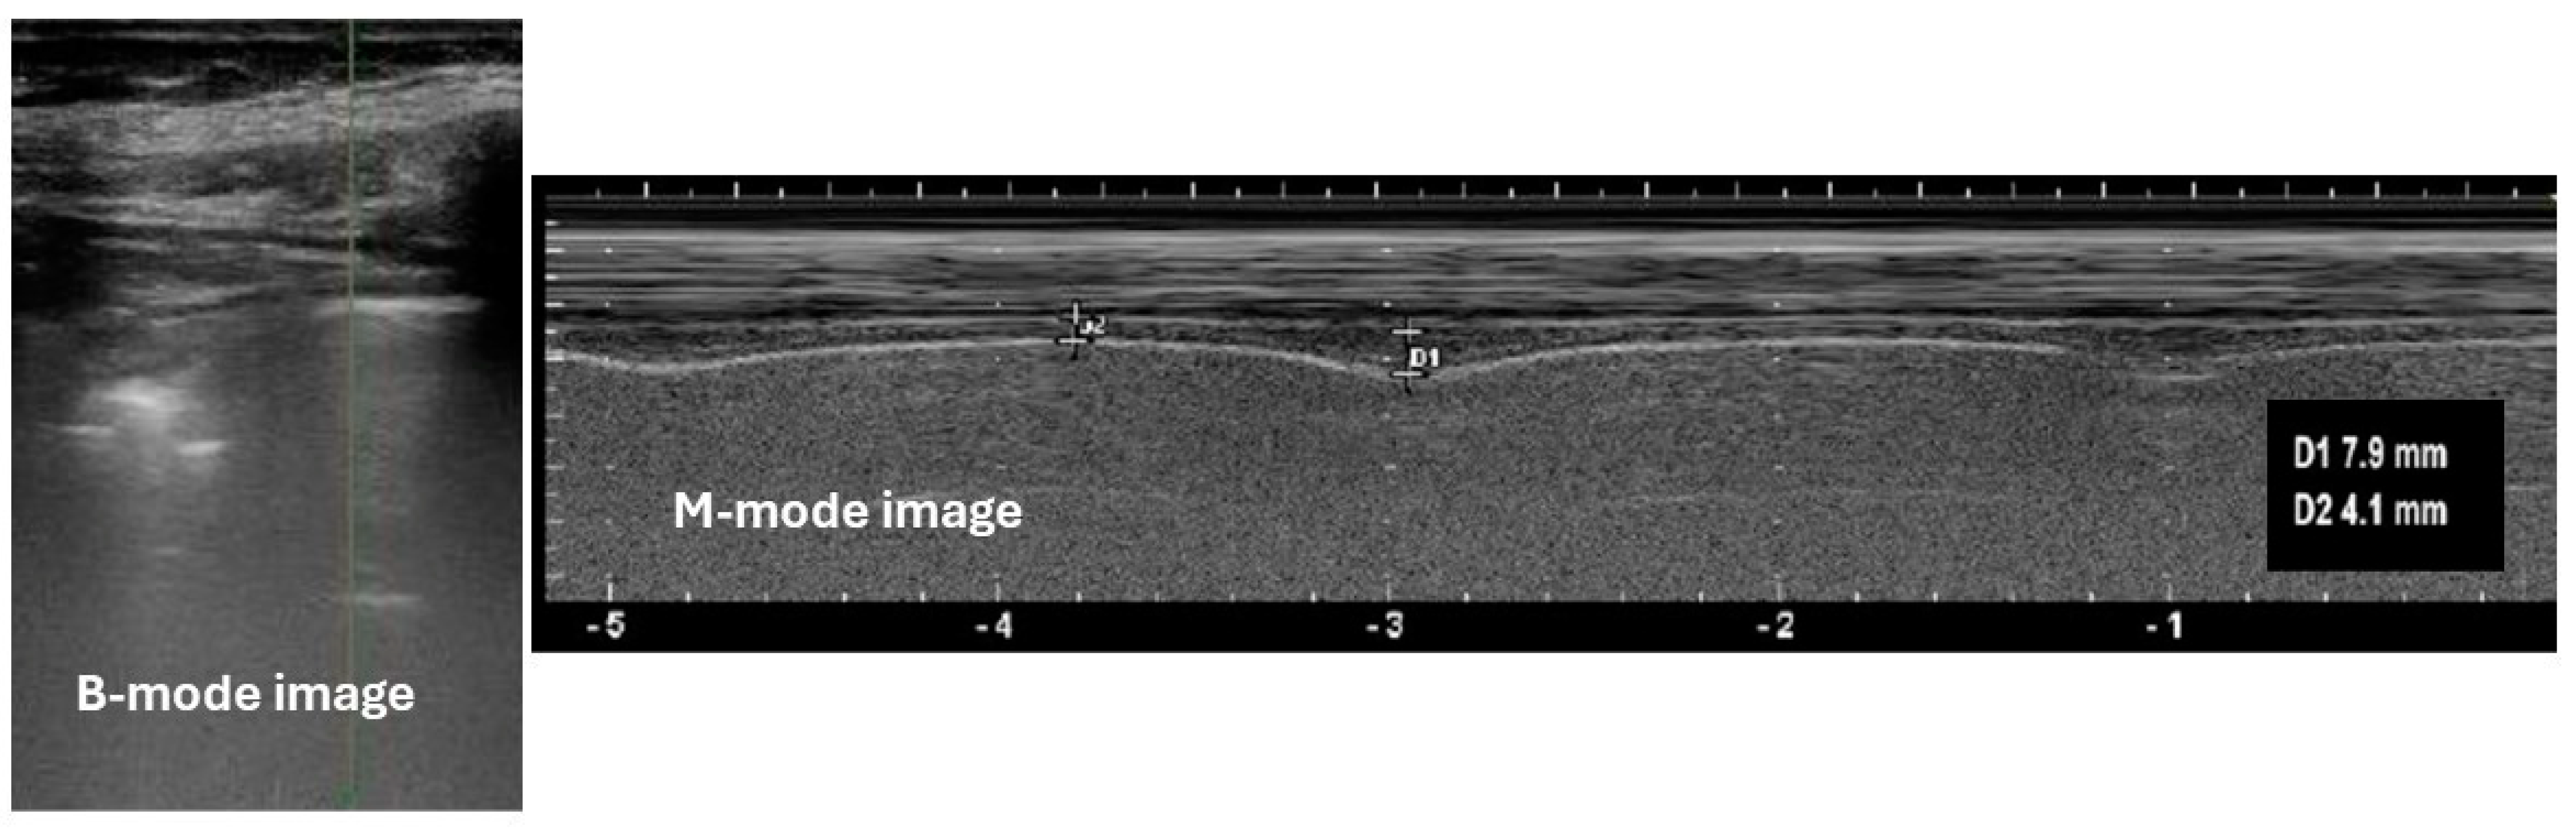

- Scarlata, S.; Mancini, D.; Laudisio, A.; Antonelli Incalzi, R. Reproducibility of diaphragmatic thickness measured by M-mode ultrasonography in health volunteers. Respir. Physiol. Neurobiol. 2019, 260, 58–62. [Google Scholar] [CrossRef] [PubMed]

- Boussuges, A.; Gole, Y.; Balnc, P. Diaphragmatic motion studied by M-mode ultrasonography. Methods, reproducibility, and normal values. Chest 2009, 135, 391–400. [Google Scholar] [CrossRef] [PubMed]

- Testa, A.; Soldati, G.; Giannuzzi, R.; Berardi, S.; Portale, G.; Gentiloni Silveri, N. Ultrasound M-mode assessment of diaphragmatic kinetics by anterior transverse scanning in healthy subjects. Ultrasound Med. Biol. 2011, 37, 44–52. [Google Scholar] [CrossRef] [PubMed]